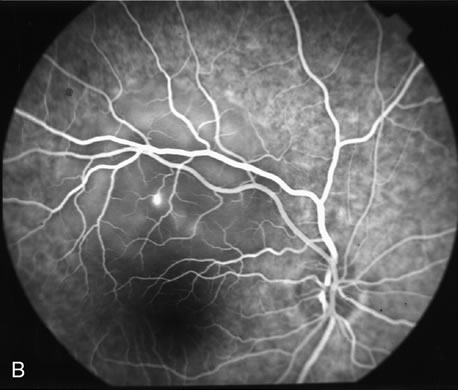

Fig. 20. A. Red-free photograph of a 20-year-old patient with sudden loss of vision to the level of 20/200. There is exudative, neurosensory macular detachment, a few hemorrhages, and lipid exudates. B. Fluorescein angiography reveals the presence of classic choroidal neovascularization (CNV), which appears to be juxtafoveal (<200 μ from fixation). Given the size of the CNV and its proximity to the fovea, it was decided to treat the patient with photodynamic treatment (PDT). C. Red-free photograph of the same eye 2 weeks after PDT; there is increased subretinal exudation D. Fluorescein angiography demonstrates that the CNV is still actively leaking. E. Red-free photograph 4 weeks after PDT demonstrates further increase in the size of the neurosensory macular detachment, subretinal hemorrhages, and lipid exudation. F. Fluorescin angiography reveals that the CNV has extended under the fovea. Given the young age of the patient, an inflammatory component of the neovascular process was suspected. It was decided to give a posterior, subtenon injection of triamcinolone acetonide, 40 mg/1 mL. G. Two weeks after steroid treatment there is partial reabsorption of the subretinal fluid. H. Fluorescein angiography demonstrates contraction of the CNV. I. Four weeks after injection of triamcinolone there is further reduction in the degree of neurosensory detachment; vision had improved to 20/60. J. Fluorescein angiography demonstrates that the CNV is smaller and less active (less leakage).

FA is needed to assess response to laser photocoagulation of a CNV and to diagnose recurrent membranes.51,54 The authors generally obtain angiograms 2 weeks, 1 month, 3 months, and 6 months after treatment. The risk of recurrence is greatest during the first 3 months, and the patient, who often has decreased vision due to prior neurosensory detachment, may be asymptomatic. FA is also needed to evaluate the results of PDT. In the original protocol of the Verteporfin in Photodynamic Therapy (VIP) and Treatment of Age-Related Macular Degeneration with Photodynamic Therapy (TAP) studies, a fluorescein angiogram was obtained every 3 months, and if there was persistent leakage from the CNV PDT was applied again (see Fig. 1820).60